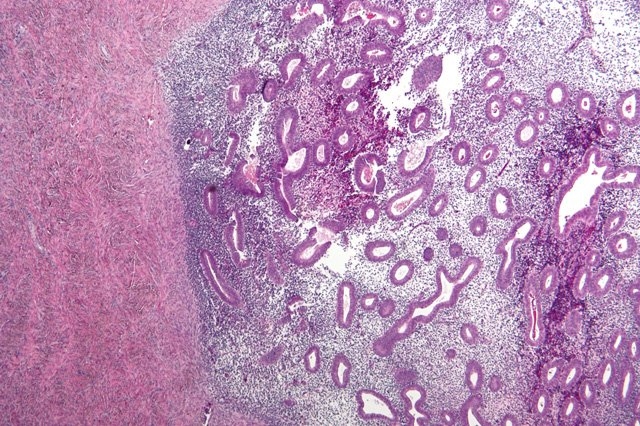

A micrograph showing endometriosis (right) and ovarian stroma (left).

Caption: A micrograph showing endometriosis (right) and ovarian stroma (left).

Endometriosis, the invasive displacement of uterine tissue into surrounding organs, affects at least 10 percent of women. The disease, which is often misdiagnosed, can cause severe pain and infertility, but very little is known about how it arises.

In patients with endometriosis, cells from the lining of the uterus flow into the fallopian tubes and then into the peritoneal cavity, where they implant on organs including the ovaries, colon, and diaphragm. This produces lesions that can cause pain ranging from mild to debilitating, and can lead to infertility.